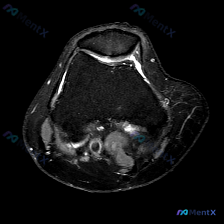

本次分析基于1张膝关节T2加权轴位MRI(髌股关节层面),临床提示为「软骨异常」,具体临床症状未提供。

- 髌股关节结构:髌骨位于滑车槽中央,对位关系尚可,无明确脱位/半脱位;关节间隙无狭窄,仅可见少量生理性高信号积液,无滑膜增厚

- 软骨与骨:髌骨及股骨髁骨皮质连续低信号,髌骨后方及滑车软骨轮廓平整,信号未见明显异常,未见明确局灶性软骨缺损或软骨下骨异常信号

- 其他结构:腘窝血管信号正常,周围肌肉、皮下软组织信号均匀,无水肿或异常占位